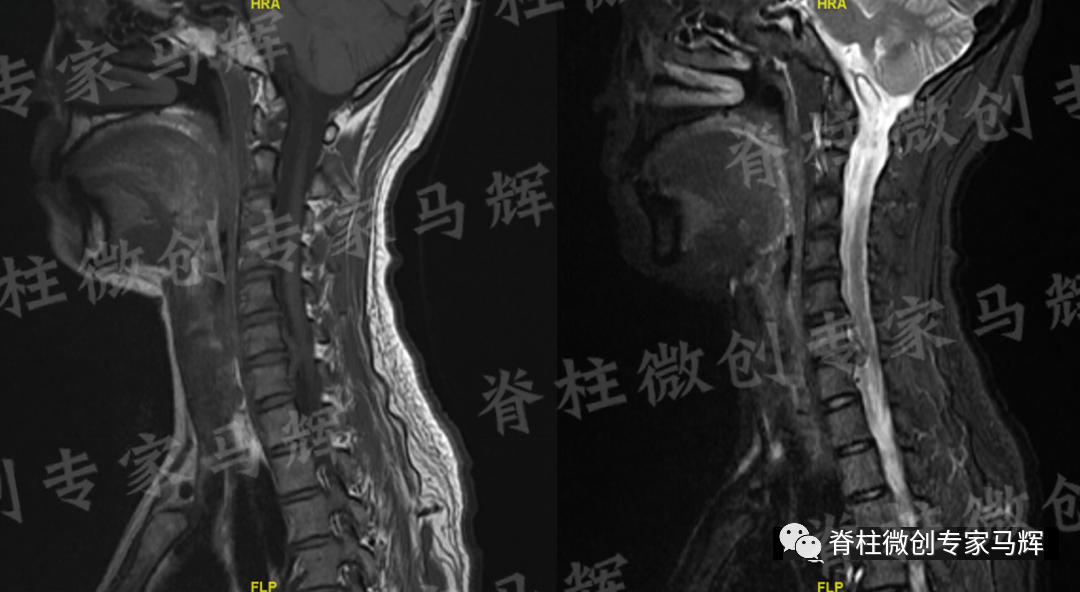

马主任仔细给患者做了检查,发现疼痛范围累及颈背部,及右上臂、前臂至手掌桡侧三指,无胸背部束带感,无行走不稳。根据影像学结果,诊断缪女士患6/7椎间盘突出症,属于神经根型颈椎病。

(术前)

经过充分准备,一周后马主任带领手术团队为患者做了颈椎后路经皮内镜下颈椎间盘髓核摘除术。手术过程十分顺利,仅用时45分钟,且手术切口很小,约8毫米。